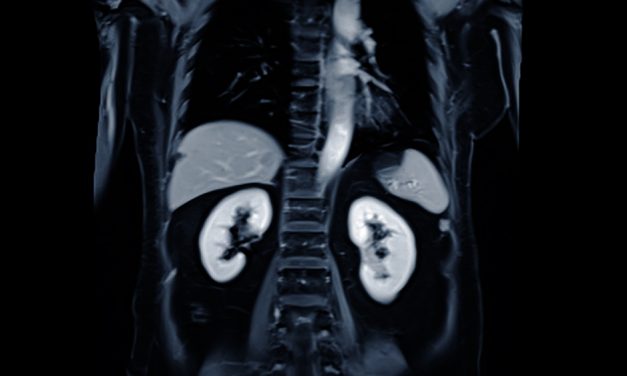

Painkillers and Kidney Health: What You Should Know

TL;DR Regular use of common painkillers—including acetaminophen (Tylenol) and nonsteroidal...

People with pre-existing kidney disease—and those with conditions that stress the kidneys, such as...